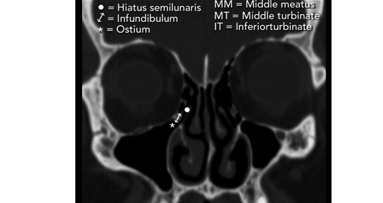

Cone Beam Computed Tomography (CBCT) is playing an increasingly important role in diagnosis and treatment planning of dental implants, and can serve as an ...